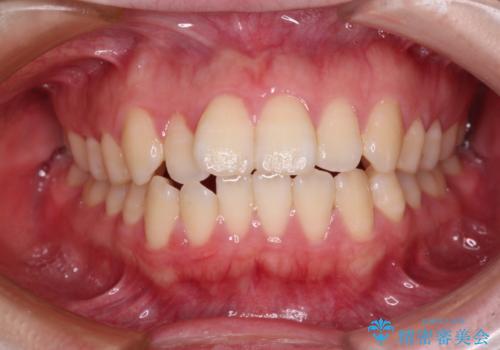

矯正歯科治療 → 上下顎前突(口ゴボ)

- デコボコと出っ歯 抜歯矯正でスッキリとした口元に